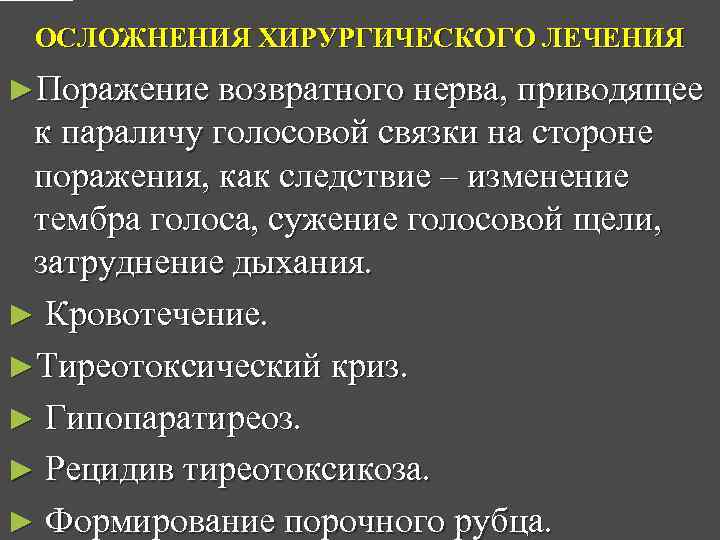

ОСЛОЖНЕНИЯ ХИРУРГИЧЕСКОГО ЛЕЧЕНИЯ ►Поражение возвратного нерва, приводящее к параличу голосовой связки на стороне поражения, как следствие – изменение тембра голоса, сужение голосовой щели, затруднение дыхания. ► Кровотечение. ►Тиреотоксический криз. ► Гипопаратиреоз. ► Рецидив тиреотоксикоза. ► Формирование порочного рубца.